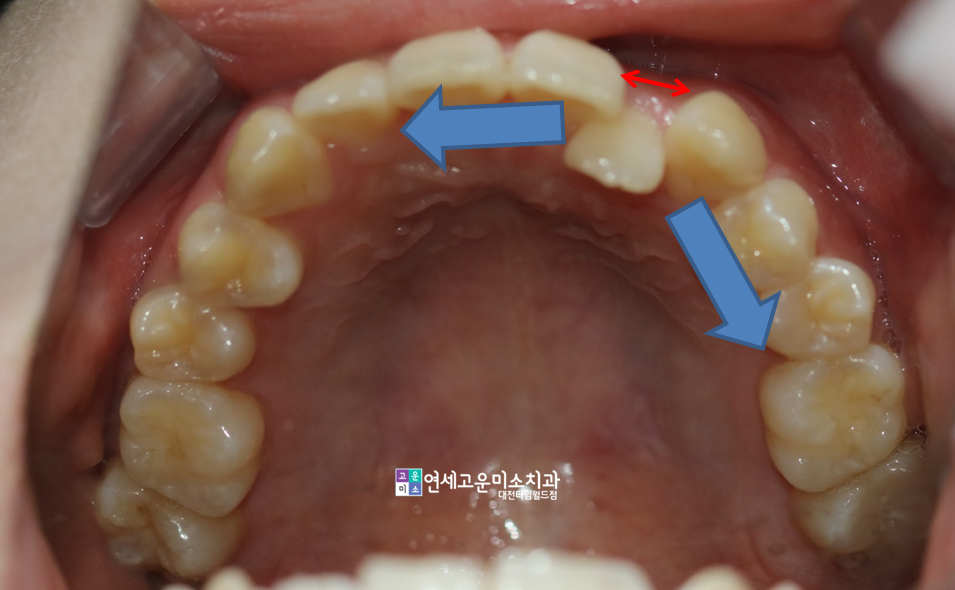

<앞니가 불규칙해요>

앞니가 불규칙한 상태로써,

상악 좌측과 하악 오른쪽의

치아들이 불규칙한 정도가

심한 편임을 알 수 있습니다.

덧니가 심한 쪽은 그쪽으로

공간 소실이 많이 일어난 것입니다.

그래서 윗니는 오른쪽으로

아랫니는 왼쪽으로 치우쳐졌고,

중심선이 어긋나게 되었습니다.

(빨간색으로 표시한 부분)